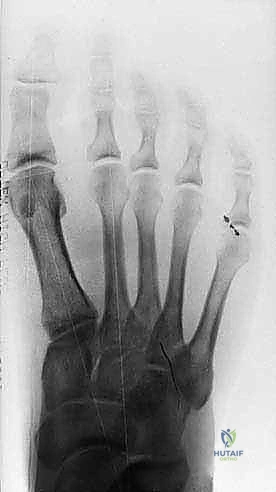

Figure 3: Anteroposterior view of a foot demonstrating a classic bipartite tibial sesamoid.

Figure 3: Another AP view of a bipartite sesamoid.

* Differentiating Bipartite Sesamoid from Fracture: This can be challenging. A fracture line is often sharp and irregular, while a bipartite sesamoid typically has smooth, well-corticated margins. AP radiographs taken in neutral and dorsiflexion can sometimes reveal separation of sesamoid segments in an unstable fracture.

FIG 10 • Preoperative ( A ) and postoperative ( B ) standing radiographs of the foot showing no change in the clinical alignment of the metatarsophalangeal joint after tibial sesamoidectomy. (From Lee S. Technique of isolated tibial sesamoidectomy. Techn Foot Ankle Surg 2004;3:85–90, with permission.)